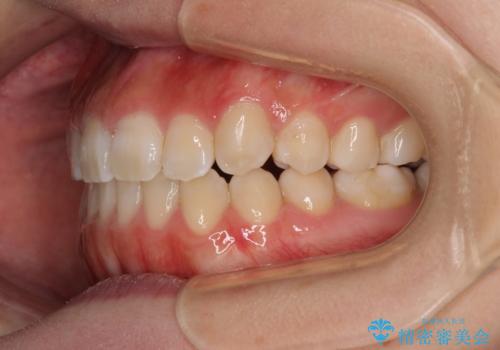

上顎骨を拡大することで、八重歯やデコボコを歯列に収めることができ、下顎の歯が外に位置していた奥歯の咬み合わせも改善することができました。

スペースも短期間に獲得できるため、1年程度で治療を終えることができました。